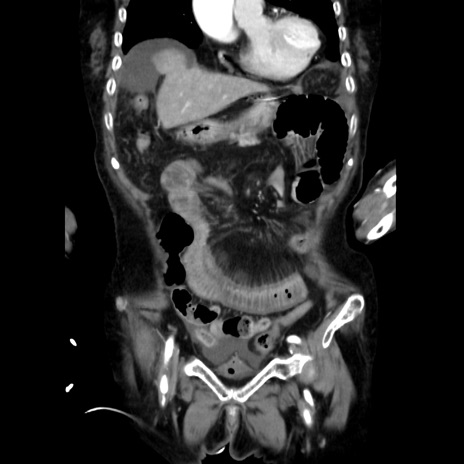

症例40(冠状断像)

他院CT

冠状断像